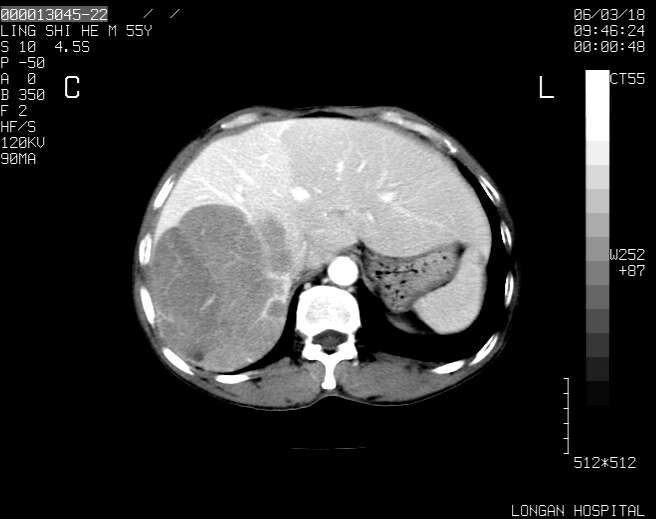

以下是引用guzhongliangddd在2006-3-21 22:13:00的发言:[br]病灶主要位于肝右叶的后份,内见异常血管,门脉主干及右支受侵{提示有癌栓形成},门腔间隙内见增大淋巴结。肝左叶内未见异常。

以下是引用zhuxinli在2006-3-22 1:23:00的发言:[br][br] 病灶主要位于肝右叶的后份,内见异常血管 .门脉右支截断,右叶前段早期强化(考虑动静脉漏),腹膜后肿大淋巴结,病灶逐渐强化,考虑为胆管细胞癌[br]